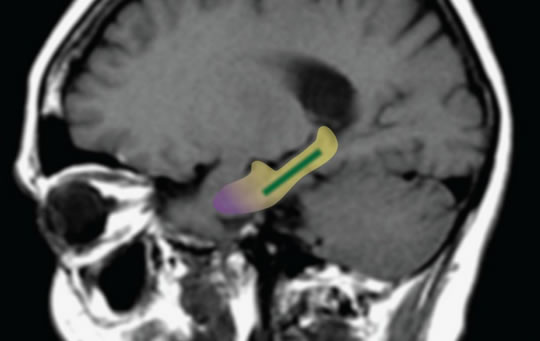

The image below shows the dentate gyrus in green (this is part of the hippocampus).

Previous research has shown that it is changes in this area of the brain that are associated with normal age-related memory loss.